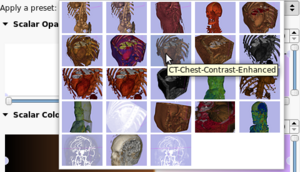

| qSlicerPresetComboBox |

|

A combobox to select presets |